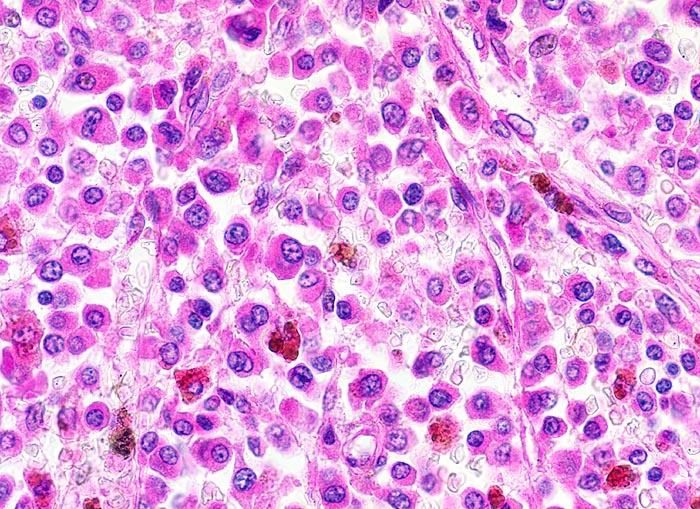

• In den hyperzellulären Arealen dichte Rasen neoplastischer atypischer Plasmazellen.

• In dieser Giemsa-Färbung sind die Plasmazellen gut erkennbar. Die Plasmazellen sind polymorph, vereinzelt mehrkernig. Exzentrisch im Zytoplasma lokalisierte vergrösserte Radspeichenkerne . Reichlich violettes Zytoplasma mit paranukleärer Aufhellung. Zellkerne teils mit vergrössertem Nukleolus.